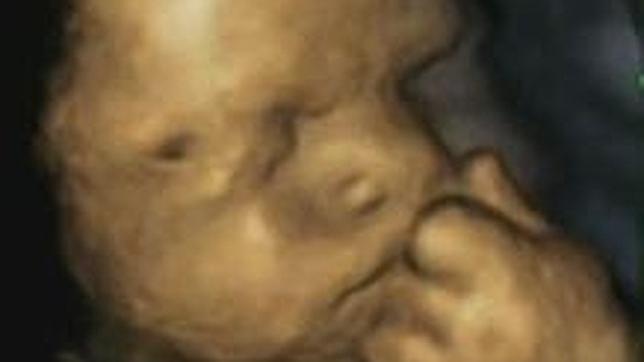

Los bebés también se estresan antes de nacer. Las futuras mamás pueden transmitirle esta inquietud al feto y la manera que tienen de expresarlo es moviendo su manita izquierda hacia la cara, de acuerdo a un nuevo estudio. Solo hay que ver la tierna ... foto que ilustra la investigación y que muestra a un bebé con el puño sobre la boca en un gesto que parece de preocupación.

Para llevar a cabo el estudio, se utilizaron ecografías en 4D , mediante las que se pudo observar a 15 bebés y grabar 342 momentos en los que se tocaban la cara.

Las imágenes se tomaron en cuatro etapas diferentes, entre la semana 24 y la 36 de gestación. También se preguntó a las madres cuánto estrés habían experimentado en las semanas transcurridas entre las ecografías. Los investigadores descubrieron que cuanto más estrés había sufrido la madre, mayor era la frecuencia con la que el feto se tocaba la cara con su mano izquierda.